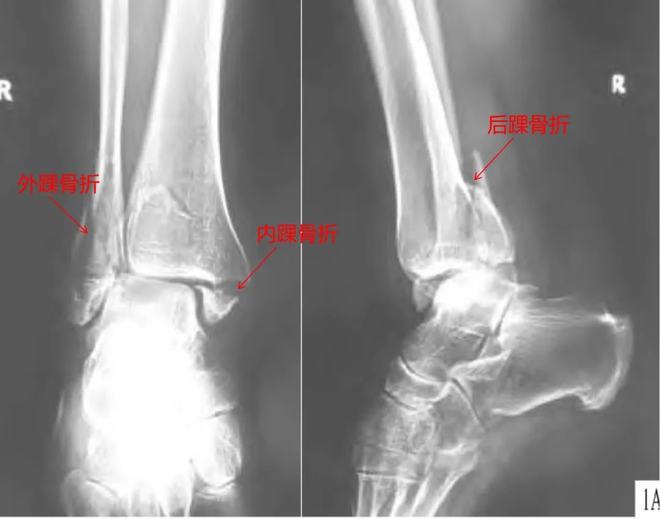

直到出院看了诊断书,我才清楚的知道自己的伤情。我的左脚内踝、外踝和后踝均骨折,也就是所谓的三踝骨折,其中一踝是粉碎性的。另外,我的踝关节也脱臼了。医生做的复位手术,就是为了让脱臼的关节恢复到原来的位置。

笔者的三踝骨折是踝关节骨折中比较严重的一种类型,三踝骨折除了内外踝骨折外,还合并胫骨远端后踝骨折,是一种严重而复杂的关节内骨折,通常伴有踝关节脱位。对于像笔者这样不能进行急诊手术的三踝骨折合并踝关节脱位患者,通常需要先将脱位复位,石膏固定,待肿胀消退后再进行手术,这样可以有效保留踝关节功能。

三踝骨折X光图丨参考1

踝部骨折手术的最佳时机是什么时候?一般来说,手术的最佳时间是受伤后6小时内,即踝部明显肿胀、水泡出现之前。此时紧急手术切开、复位、固定骨折,可减少血肿,利于切口一期缝合,从而减少患者痛苦,缩短住院时间。

但大多数情况下患者就诊时踝关节肿胀已经很明显,部分患者可能还会出现如笔者一样的张力性水疱,此时必须推迟手术。骨折后组织损伤,局部渗出物增多,因组织压力不均而出现张力性水疱。